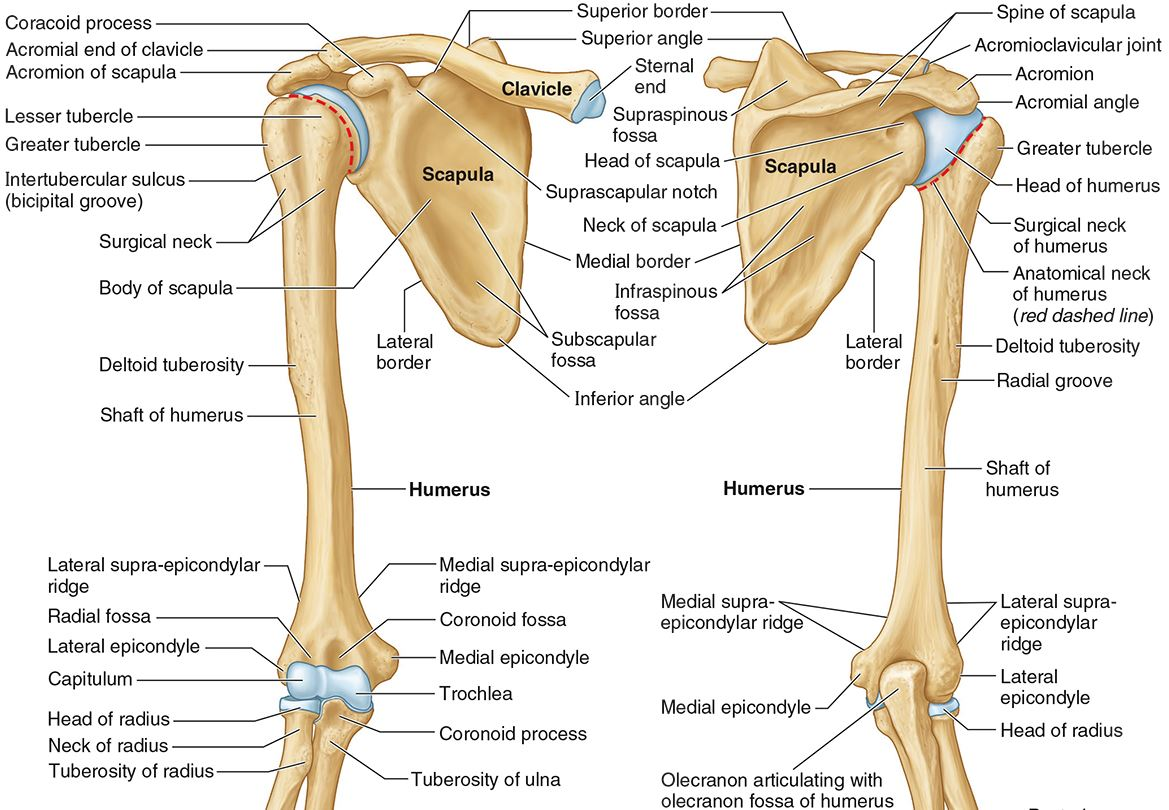

What part of the humerus is this?

The head of the humerus articulates with the scapula at the glenohumeral joint.

What part of the humerus is this?

The anatomic neck is an indentation distal to the head and provides an attachment for the fibrous joint capsule of the glenohumeral joint.

What part of the humerus is this?

The greater tubercle lies lateral and distal to the anatomic neck.

What part of the humerus is this?

The lesser tubercle lies on the anterior/medial side of the humerus, just distal the anatomic neck.

What part of the humerus is this?

The intertubercular (bicipital) groove lies between the greater and lesser tubercles.

What part of the humerus is this?

The surgical neck is a narrow area distal to the tubercles. It is a common site for proximal humerus fractures.

What part of the humerus is this?

The humeral shaft features the deltoid tuberosity laterally for the distal insertion of the deltoid muscle.

What part of the humerus is this?

The radial groove is an oblique depression that contains the radial nerve and deep brachial artery.

Which parts of the humerus is this?

The medial and lateral epicondyles are distal prominences to which many forearm tendons attach, near the elbow joint.

Which parts of the humerus is this?

The medial and lateral supracondylar ridges extend superiorly from the medial and lateral epicondyles.

Which parts of the humerus is this?

The trochlea and the capitulum (the condyles) are the most distal surfaces of the humerus, where it articulates with the forearm bones at the elbow joint

What part of the humerus is this?

The olecranon fossa is a posterior depression above the trochlea that receives that olecranon process of the ulna

What part of the humerus is this?

The coronoid fossa is an anterior depression above the trochlea that receives that coronoid process of the ulna.